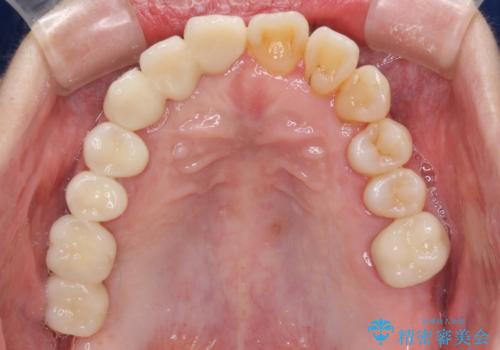

数多くの外科処置を行ったため、治療期間は長期間となりました。

一方、外科処置をしっかりと行ったことで、歯周病の状態は改善され、安定した状態にしあげることができました。